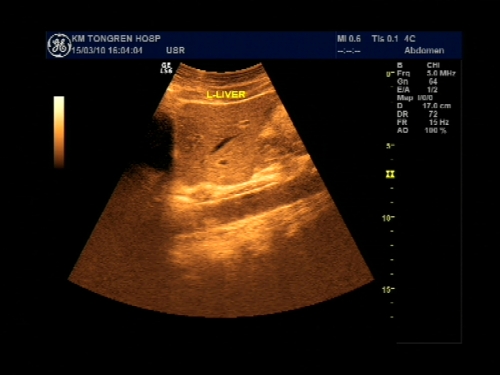

超声声像图能显示肝脏切面形态、大小、肝内实质结构、管道系统及肝周邻,并能根据肝内管道系统区分肝脏各叶、各段,对病变进行定位诊断。彩色多普勒超声能显示肝脏的血流,并能对肝脏的血流动力学参数进行测定,不仅能诊断肝脏的血管病变,还能了解正常肝脏及病变肝脏的血供及回流状态,目前已成为临床诊断肝脏疾病的常规检查方法。

纵断扫查

横断扫查

冠状断面扫查